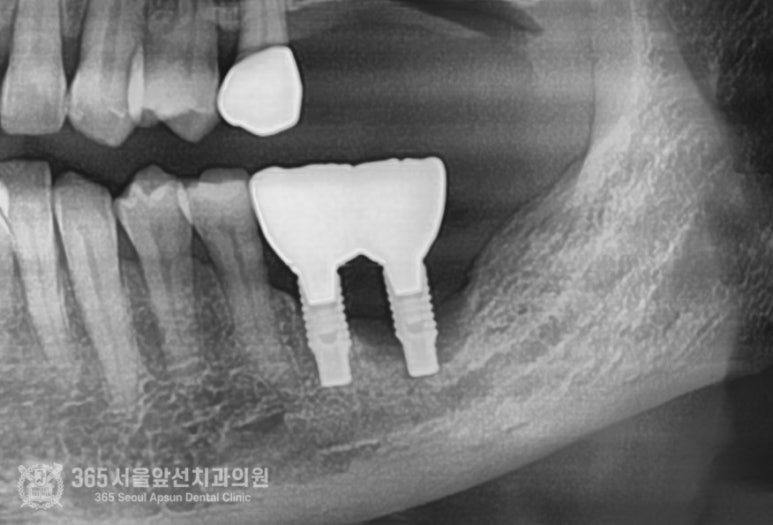

촬영일시: 2024.07.07. 제거하고 대략 2개월 정도 지나고 엑스레이입니다. 뼈가 움푹 파여서 이 상태로는 임플란트 식립이 어려운 상황입니다. 촬영일시: 2024.08.10. 골이식과 동시에 임플란트를 식립하였고 사진의 노란색 부위만큼이 골이식이 들어간 부위입니다. 이 환자분의 증례에서 시행된 골이식술은 수직골증강술이라는 매우 고난이도 술식입니다. 하지만 숙련된 의료진과 함께라면 걱정안하셔도 되겠습니다 ㅎㅎ 촬영일시: 2024.10.10. 약 5개월 정도 지난 후 잇몸을 열어서 이식된 골이 잘형성되었는지 확인함과 동시에 임플란트도 뼈와 잘결합되었는지 확인합니다. 다행히 뼈 형성도 좋고, 임플란트도 단단하게 잘 붙었습니다 ㅎㅎ